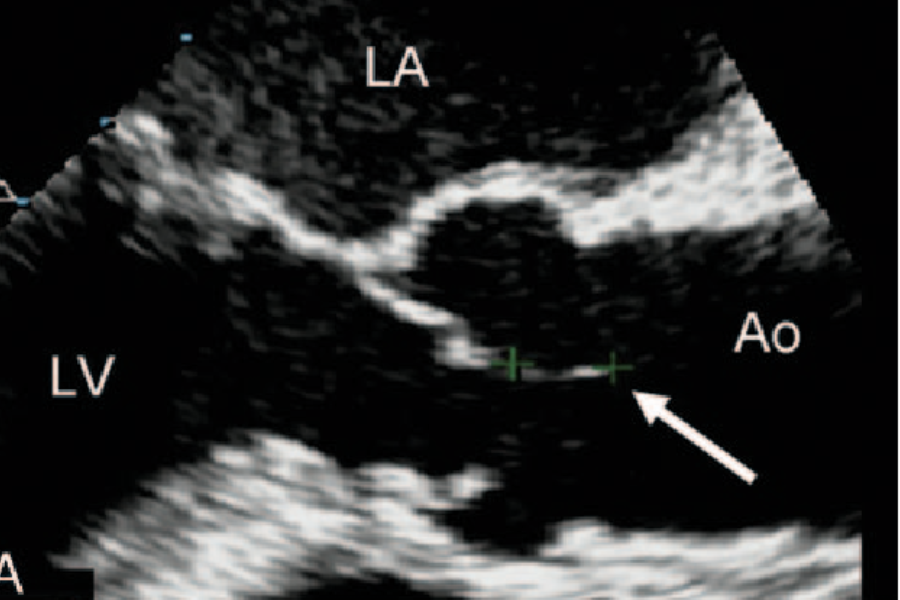

Q

This short-axis of the aortic valve in the figure shows?

A

Papillary fibroelastomas are benign tumors that can be seen on the aortic valve. These tumors are described as small, well-delineated, pedunculated masses with a predilection for valvular endocardium. These tumors can be highly mobile and carry an embolic risk. The diagnoses are usually incidental or during investigation for an embolic source. The echocardiographic characteristics of fibroelastomas are:

The tumor is round or oval, irregular in appearance, with well-demarcated borders and a homogeneous texture.

Most are relatively small <20 mm.

Nearly half have small stalks, and those with stalks are mobile.

They may be single or multiple and are often associated with valvular disease.

They more commonly appear on the aortic valve, followed by the mitral valve.